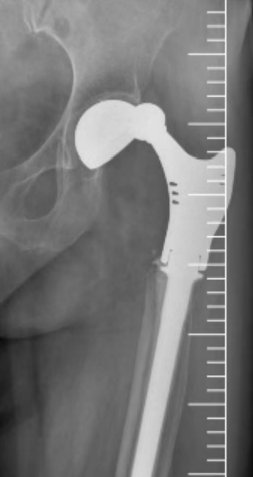

接诊后,北京积水潭医院郑州医院骨病与骨肿瘤科主任秦光华团队展开全面评估,影像学检查显示多重棘手问题:

人工髋关节脱位明确且假体松动明显,

患侧脱位后解剖结构紊乱,进一步增加治疗难度。

术前X线影像检查

临床数据显示,此类肿瘤术后髋关节翻修手术的难度系数是常规翻修手术的 3 倍以上,对手术团队的解剖认知、操作精度及应急处理能力均提出极高要求。